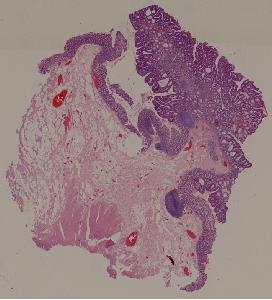

28.结肠腺瘤